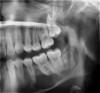

Figure 3 Examples of using digital workflow to import restoration data and plan implant treatment: the intraoral scan (IOS) data pinned to the CBCT (Fig 3); the designed ideal restoration being imported into the CBCT (Fig 4); the implant placed with the restoration and IOS toggled off (Fig 5).

Figure 3

Although workflows can vary, in many implant cases, typically a CBCT scan of the area of concern is made. Then, with an intraoral scan or digital version of a model or impression, the practitioner begins working with the design software of the particular intraoral scan or CBCT system being used (Figure 3 through Figure 5). The edentulous area or area where teeth are to be extracted can then be thoroughly evaluated. Ideal restorations can then be previsualized or treatment planned from both an esthetic and functional standpoint. Once this is done, the intraoral information is pinned or overlaid onto the CBCT scan. The restoration(s) can then be imported into the software system, toggled on or off—ie, shown or not—and the underlying bone evaluated.3

If the ideally designed restorations cannot be supported by available bone, additional surgical procedures, such as grafting, may be indicated. Implants can be placed in 3-D in the ideal location for esthetics and function, allowing the practitioner to visualize where osseous grafting may be needed to achieve that positioning. Alternatively, implants can be virtually positioned based on the available anatomy, respecting anatomical structures such as the inferior alveolar nerve, maxillary sinus, and the buccal/lingual plates (Figure 6 and Figure 7). This restorative-driven implant placement workflow allows general practitioners to see what may be needed to augment bone to support ideal restorations. This may alert them to the need for additional surgical procedures or to open further dialogue with surgical team members.